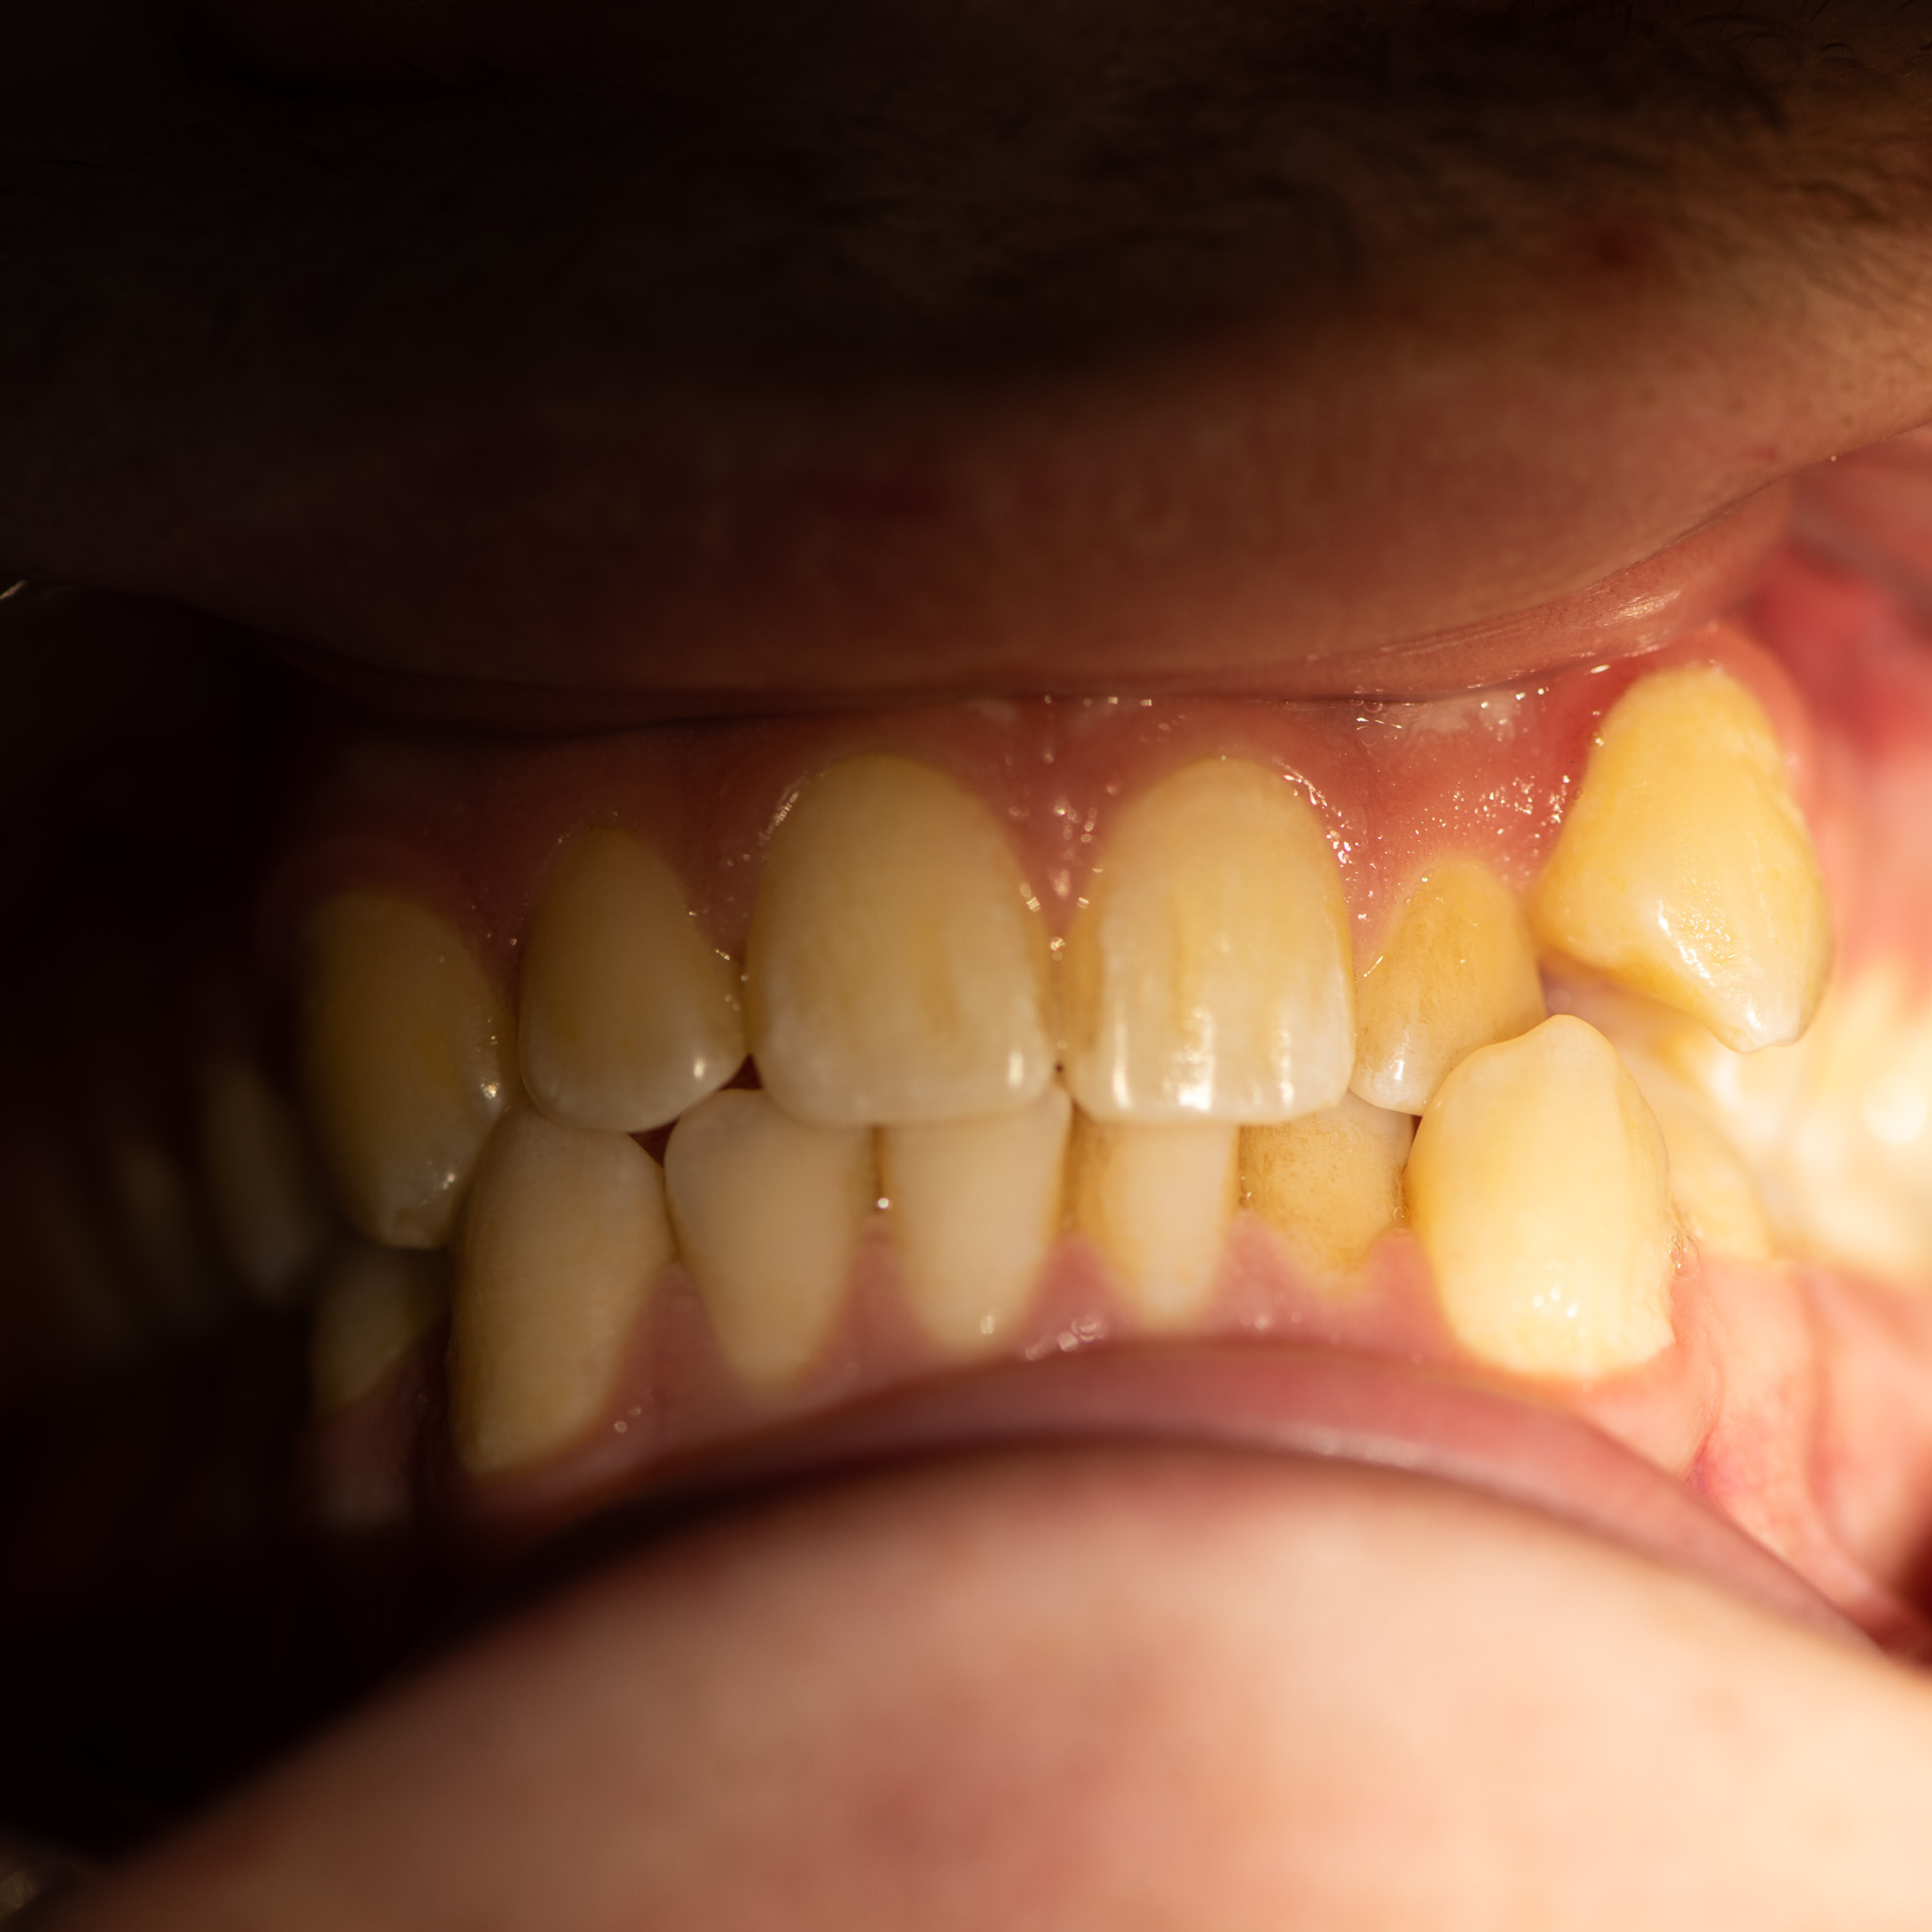

Фотографии учеников до обучения